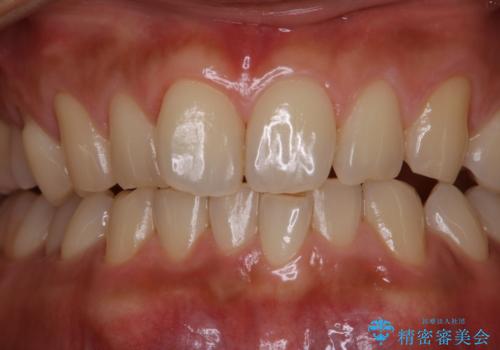

表のワイヤー装置で矯正中にPMTCで綺麗にお掃除

担当医 歯科衛生士